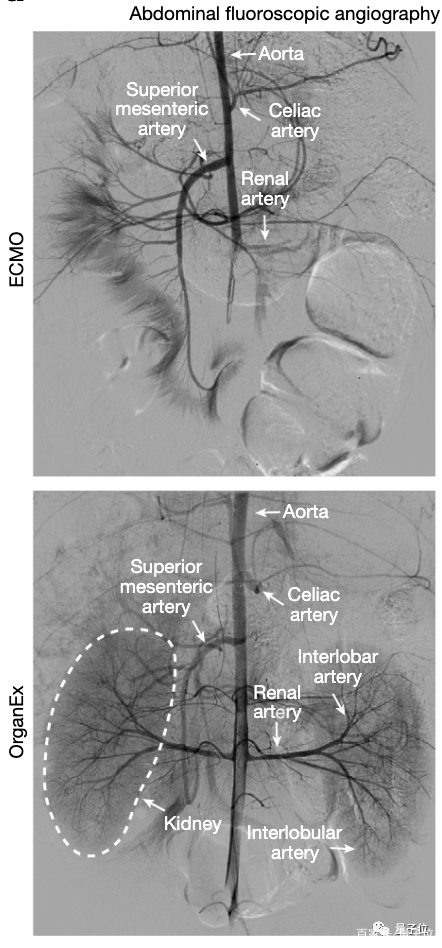

OrganEx比“人工肺”ECMO复杂一些,除了心肺,还模仿了肾的功能,具体包括离心泵、脉冲发生器、血液透析滤过仪、气体输注/药物输送系统和传感器(用于测量代谢和循环参数)。

结果是OrganEx成功在小猪体内恢复了全身血液循环,各处动脉和器官(心脏、脑、肾和肝等)保持“充盈”状态,在ECMO则只能看到非常有限的此类现象。